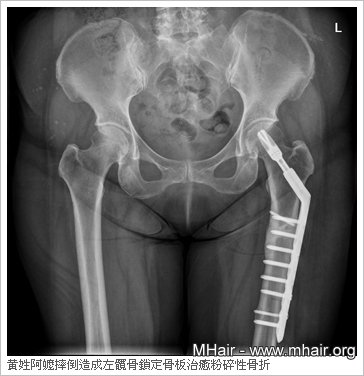

释高 上医师表示,一名75岁的黄姓阿嬷为骨质疏松症病患,日前上门求诊,她有15年高血压、心律不整、关节炎等病史,一年多前因跌倒而造成左髋骨“粉碎性骨 折”。由于骨质疏松和骨折粉碎,无法使用传统的骨钉骨板固定手术,经评估后改以“锁定式骨板微创手术”进行治疗,患者于术后恢复良好。

释高上医师说明,“锁定式骨板”的洞口具有螺纹,骨钉栓进骨头后,可与骨板紧紧锁住,明显分担骨头的支撑力,结构角度稳定、不易松脱。其与骨骼接触面采小面积接触设计,可减轻对外骨膜的压迫、保存血液供应、加速骨骼愈合,大幅降低住院时间。